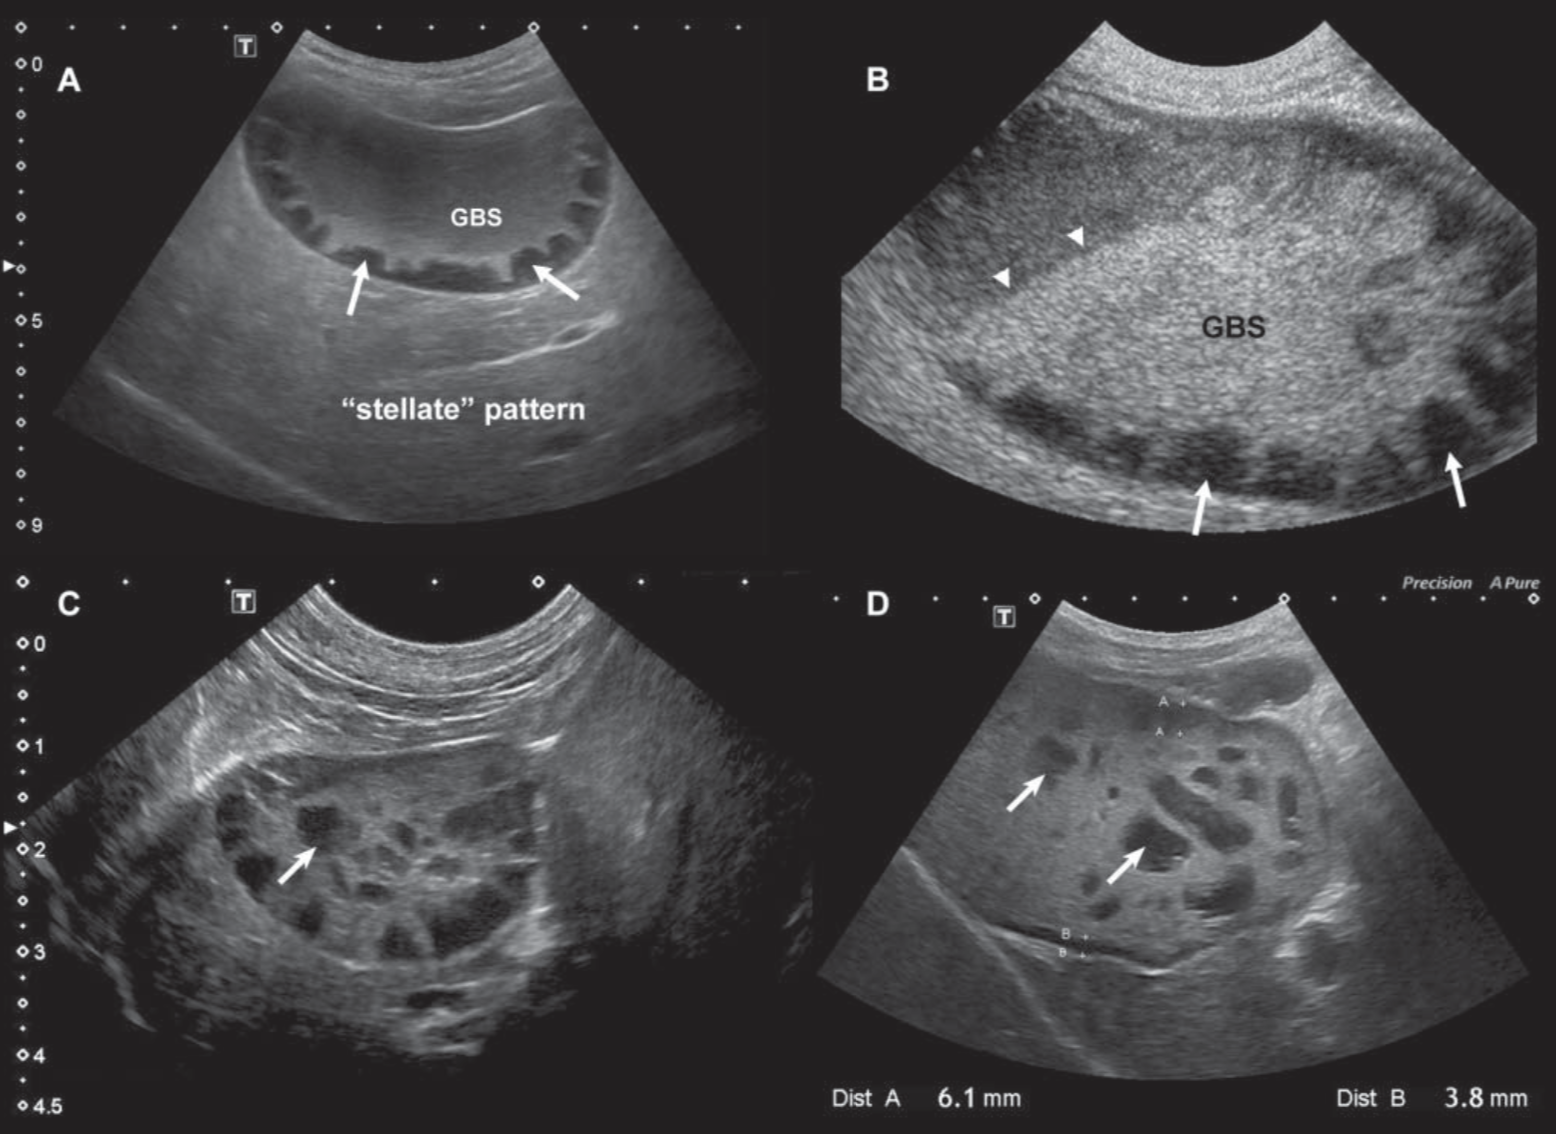

犬 胆泥症 原因-胆泥 をかたちづくっているのは コレステロール や 黄疸色素 ( ビリルビン )、 カルシウム などの微細な 結晶 が 胆嚢壁 から分泌される 粘液 に包まれたものと考えられますが、他にも 炎症 によっこんにちは。獣医師の清水いと世です。 今回は、わんちゃんの胆泥症について説明します。 前編は、胆泥症の原因や検査方法や症状について、後編は治療や予防方法について説明します。 犬の胆泥

胆泥症・胆石症について 胆嚢は、胆汁を産生し貯留する器官です。 胆汁には、脂肪を分解し水に溶けやすい状態に(乳化)する役割を持っています。 胆嚢に貯えられた胆汁は、元々サラサラの水胆泥を生じさせた原因や疑われる原因があれば、それを取り除きます。 そのために、 犬の胆泥症 <前編> で説明した原因追及のための検査結果が重要になります。 肝臓の異常が認められるので